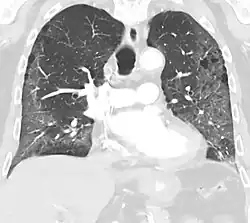

High-resolution CT image showing ground-glass opacities in the periphery of both lungs in a patient with COVID-19 (red arrows). The adjacent normal lung tissue with lower attenuation appears as darker areas.

CT image in patient with COVID-19 showing bilateral ground-glass opacities at the periphery of both lungs.

Ground-glass opacity is among the most common imaging findings in patients with confirmed COVID-19.[16][17] One systematic review found that among patients with COVID-19 and abnormal lung findings on CT, greater than 80% had GGOs, with greater than 50% having mixed GGOs and consolidation.[16] GGOs with mixed consolidation has most often been found in elderly populations.[18] Several studies have described a pattern among initial, intermediate, and hospital discharge imaging findings in the disease course of COVID-19. Most commonly, initial CT imaging reveals bilateral GGOs at the periphery of the lungs. During initial stages, this is most often found in the lower lobes, although involvement of the upper lobes and right middle lobe has also been reported early in the disease course.[16][18] This is in contrast to the two similar coronaviruses, SARS and MERS, which more commonly involve only one lung on initial imaging.[19][20] As the COVID-19 infection progresses, GGOs typically become more diffuse and often progress to consolidation.[11][18] This is sometimes accompanied by the development of a crazy paving pattern and interlobular septal thickening.[18] In many cases the most severe pulmonary CT abnormalities occurred within 2 weeks after symptoms began.[17] At this point, many individuals begin showing resolution of consolidation and GGOs as symptoms improve. However, some patients have worsening symptoms and imaging findings, with further increase in septal thickening, GGOs, and consolidation. These patients may develop lung "white-out" with progression to acute respiratory distress syndrome (ARDS) requiring treatment escalation.[17][21]

Preliminary reports have shown many patients have residual GGOs at time of discharge from the hospital. Due to the novelty of COVID-19, large studies investigating the long-term pulmonary CT changes have yet to be completed. However, long-term pulmonary changes have been seen in patients after recovery from SARS and MERS, suggesting the possibility of similar long-term complications in patients who have recovered from acute COVID-19 infection.[22]